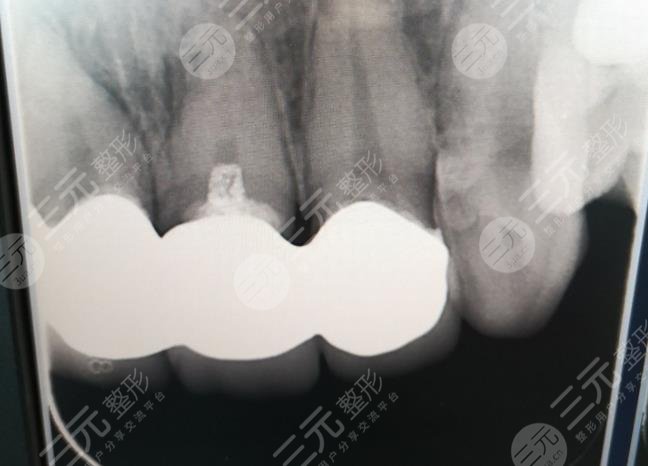

When I just finished it, I still feel a little uncomfortable, I always feel that there is something more in my mouth, and I will be completely used to it after about a week, this feeling has been done in this oral cavity for almost a year, I feel very good, there is no discomfort, the teeth are not yellow, I have to say, this hospital is still very reliable, it is worth choosing.